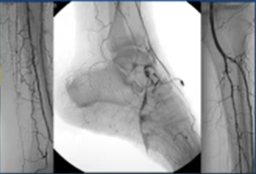

Recanalization of infra popliteal CTO + US Doppler et insuffisance veineuse